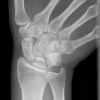

Handgelenk dorso-volar (1. Ebene)

Indikation

Fraktur

Lagerung

sitzend - seitlich zum Tisch

abgewinkelter Unterarm und die Handfläche liegen auf

Finger 2-5 werden leicht aufgestellt

Zentralstrahl

senkrecht

Querzentrierung auf Gelenkspalt

Längszentrierung auf Objektmitte

Einblendung

distal einschließlich Fingergrundgelenke

Anmerkung

Darstellung der Handwurzel- und Unterarmknochen, bei Fragestellung von Epiphysenlösung, Grünholz- oder Os scaphoideumfraktur. Zur Beurteilung der Knochenkerne bei Kindern werden Vergleichsaufnahmen notwendig, bei Verdacht auf Subluxation des Os Lunatums, Zusatzaufnahme in Flextion und Reflextion der Hand notwendig (siehe Stressaufnahme).

ggf. Tisch hochfahren

Qualitätskriterien

Vollständige Abbildung der Metacarpalia, Handwurzelknochen und distaler Unterarm.